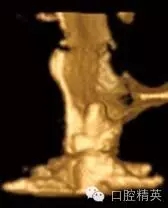

圖1c:術后用ICATCBCT進行三維立體效果再現(xiàn),顯示種植體穿入上頜竇的實踐情況

我們通過文獻和網(wǎng)站檢索獲得了一些關于種植體失敗的研究和綜述文章。一個和僅使用兩維放射診斷(根尖片或曲斷片)有關的常見失敗是上頜竇穿孔。(圖1a-c)通常牙醫(yī)由于錯誤的估計了上頜竇底骨量高度而造成幾個毫米的上頜竇底穿孔。一些病例可能沒有癥狀,象圖中所示的這個病例,患者需要嚴格的監(jiān)控、復查。有些病例則出現(xiàn)并發(fā)癥,種植體不得不取出。

另一個和醫(yī)生僅用兩維放射線檢查造成的特殊并發(fā)癥是種植體進入上頜竇。(圖2a-c)可能成為上頜竇異物的有牙齒,牙根,印模材料,牙科器械,近年來又增加了一個—種植體??上攵瑥纳项M竇中取出異物對患者來講是創(chuàng)傷很大的。

其他研究也報道過,對于這種病例,唯一的選擇是用根管顯微鏡或Caldwell Luc技術從上頜竇中取出種植體。有些文章報道了如何處理進入上頜竇的種植體,但很少從預防的角度來談這個問題,其實很簡單,術前應該應用CBCT成像檢查。